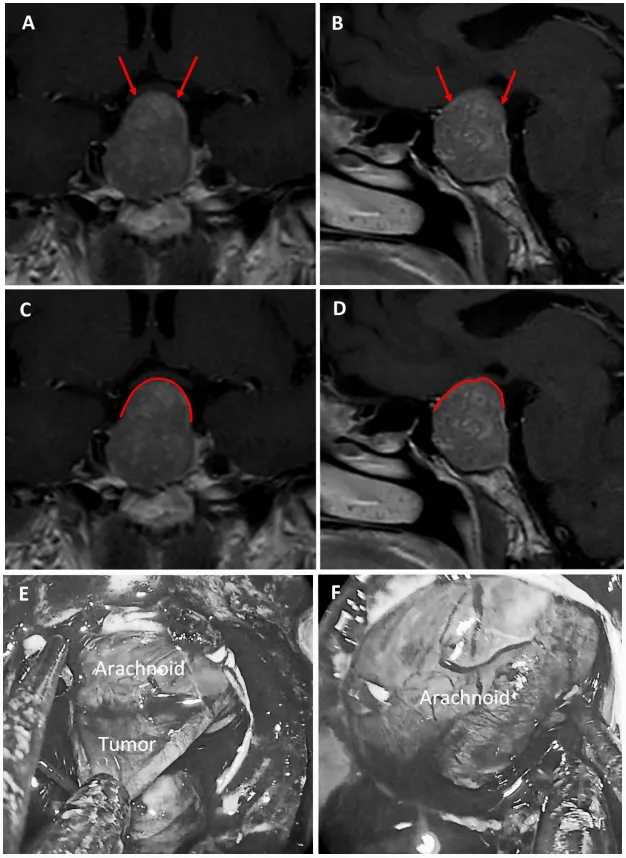

圖6:59歲女性泌乳素腺瘤患者。a、b術(shù)前MRI:紅色箭頭指示厚度小于1毫米的強化屏障區(qū)。c、d術(shù)前MRI:紅色標記線標示薄弱屏障位置。e、f術(shù)中圖像:可見由蛛網(wǎng)膜構(gòu)成的屏障結(jié)構(gòu)。